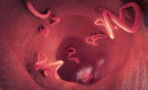

Vaginal dryness—or atrophy, as known in the medical world—affects women of all ages and backgrounds all over the world. From uncomfortable soreness to pain during sex, dehydrated vaginas are more common than you think.

Often mistaken for either vaginal or sexually transmitted infections, vaginal dryness is most commonly experienced in women going through menopause.